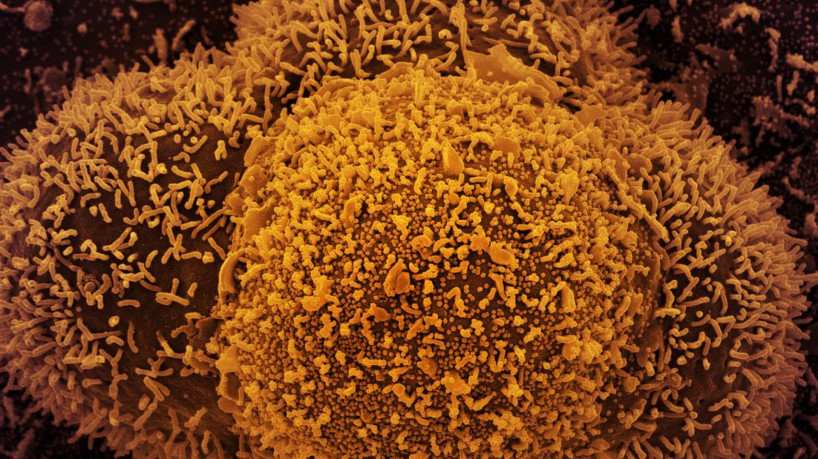

A Ômicron é uma variante da Covid-19 detectada há quase um mês e que, por seu elevado grau de transmissão, pode mudar novamente o rumo da pandemia, em especial por causa de seu impacto na vacinação. Ômicron é uma nova versão do SARS-CoV-2 (o coronavírus origem da pandemia), identificado no fim de novembro em Botsuana, e depois na África do Sul.

Sua particularidade é o grande número de mutações na comparação com a variante original que foi detectada na cidade chinesa de Wuhan, e de posteriores versões, como a delta, que domina até agora amplamente a transmissão da pandemia.

AssineNão se sabe como surgiu a ômicron. Uma hipótese em debate entre os cientistas é que o vírus teria sofrido uma lenta mutação no organismo de uma pessoa com imunodeficiência, um processo que durou vários meses, até chegar à versão atual.